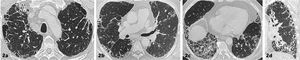

Alteraciones parenquimatosas en TCARLas principales alteraciones radiológicas que podemos encontrar son las que se describen a continuación. Cada una de estas alteraciones ofrece pistas sobre la etapa de la enfermedad y sus posibles etiologías (figura 1).

Vidrio esmerilado: Tenues opacidades pulmonares a través de las cuales se puede visualizar las estructuras vasculares y bronquiales del parénquima pulmonar subyacente. Estas alteraciones pueden indicar etapas iniciales de fibrosis o inflamación alveolar.

Consolidación: Opacidades alveolares densas que no permiten la visualización de la arquitectura vascular y bronquial. En EPID, la consolidación puede sugerir exacerbación aguda, infección secundaria o neumonía en organización, esta última especialmente asociada a enfermedades del tejido conectivo.

Patrón reticular: Red de finas líneas que representan el engrosamiento intersticial. Un patrón reticular con distorsión arquitectónica sugiere enfermedad intersticial fibrótica.

Bronquiectasias/bronquiolectasias por tracción: Dilatación irreversible de la vía aérea generalmente de morfología tortuosa e irregular.

Panal de abeja: Estructuras quísticas de paredes gruesas, agrupadas, de 3-10mm, frecuentemente localizadas en las regiones subpleural y basal. Este patrón es altamente indicativo de fibrosis pulmonar avanzada, especialmente en enfermedades como la fibrosis pulmonar idiopática. Uno de los hallazgos en que más diferencia interobservador se ha demostrado es en la identificación de la panalización, dado que puede ser difícil de diferenciar de enfisema o bronquiectasias.